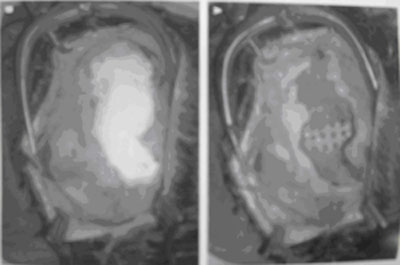

图11额部缺损修补术的术前术后对比照片

(图片来自journal of craniomaxillofacial surgery)